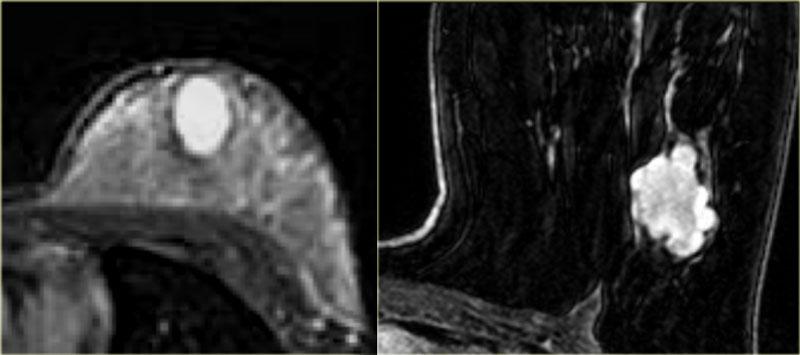

Hình ảnh bên trái cho thấy một khối lớn, bất quy tắc, được xác định là u mạch máu (angiosarcoma).

Hình ảnh ngoài cùng bên trái là u xơ tuyến vú dạng trẻ em (juvenile fibroadenoma) – có hình bầu dục với bờ nhẵn, tức là đặc điểm điển hình của tổn thương lành tính.

Các vách ngăn không ngấm thuốc không được thấy trong trường hợp này.

Hình ảnh bên phải là một ví dụ khác về u xơ tuyến vú: khối dạng thùy múi với các vách ngăn không ngấm thuốc.